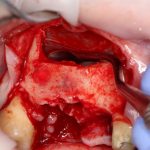

Синуслифтинг: что делать при перфорации слизистой оболочки гайморовой пазухи?